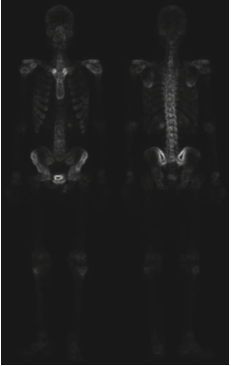

다른 방법은 어떤 방법이 있을 까요? 그 방법은 영상 그래디언트의 스무딩된 버전의 마스크를 사용하는 것입니다. 이러한 과정을 가능한 이유는 미분의 특성에 기인합니다. 라플라시안 필터는 애초에 2차 미분 연산입니다. 따라서 세세한 디테일 개선에는 좋은 결과를 얻을 수 있습니다. 하지만 노이즈가 많은 입력 영상을 받으면 출력 영상 역시 노이즈가 많게 됩니다. 하지만 로버츠나 소벨 연산과 같은 1차 미분 연산자는 라플라시안 필터에 비해서 노이즈나 미세한 디테일에 적은 반응을 보이고, 노이즈나 미세한 디테일을 얻는다고 해도 스무딩을 통해 제거 가능합니다. 따라서, 그래디언트 기반의 필터링을 통해서 엣지를 추출한 뒤 혹시나 남아있는 노이즈를 제거하기 위해 스무딩을 적용하는 것을 샤프닝된 영상의 입장에서는 골격의 마스크로 볼 수 있기 때문에 두 영상을 곱한 결과를 사용하는 것이 합리적입니다. 이를 위해서 위의 사진과 같이 입력 영상에 소벨 연산을 적용하게 됩니다.

다음으로 기울기 영상에 스무딩을 적용하여 약간의 노이즈를 제거해줍니다. 그러면 이를 마스크로 취급하고 샤프닝된 영상과 곱을 취해줍니다.

그 결과 영상 내의 강한 엣지들이 더 많이 남아있으며 노이즈는 라플라시안만 활용한 것에 비해서 더 줄어든것을 관찰할 수 있습니다. 이제 강한 엣지 영상을 샤프닝하는 데 사용해주면 됩니다.